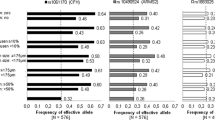

For AMD, we found a higher PRS to be borderline associated with a more likely AMD presence (per unit OR 4.99, 95%CI 0.95 to 26.23, P = 0.057) in multivariable logistic regression models. For SDD, we observed a trend of higher PRS in individuals with SDD (Fig. 1). This trend, however, was not found in the multivariable logistics regression model (OR 1.87, 95% CI 0.61 to 5.76, P = 0.27), in which only age was associated with presence of SDD. Similarly, we found only age and not the PRS to be associated with the area of SDD in the multivariable linear regression models (data not shown). We furthermore found no individual SNP to be associated with presence of SDD. Supplemental figure 2 presents a Manhattan plot for the 53 tested SNPs.